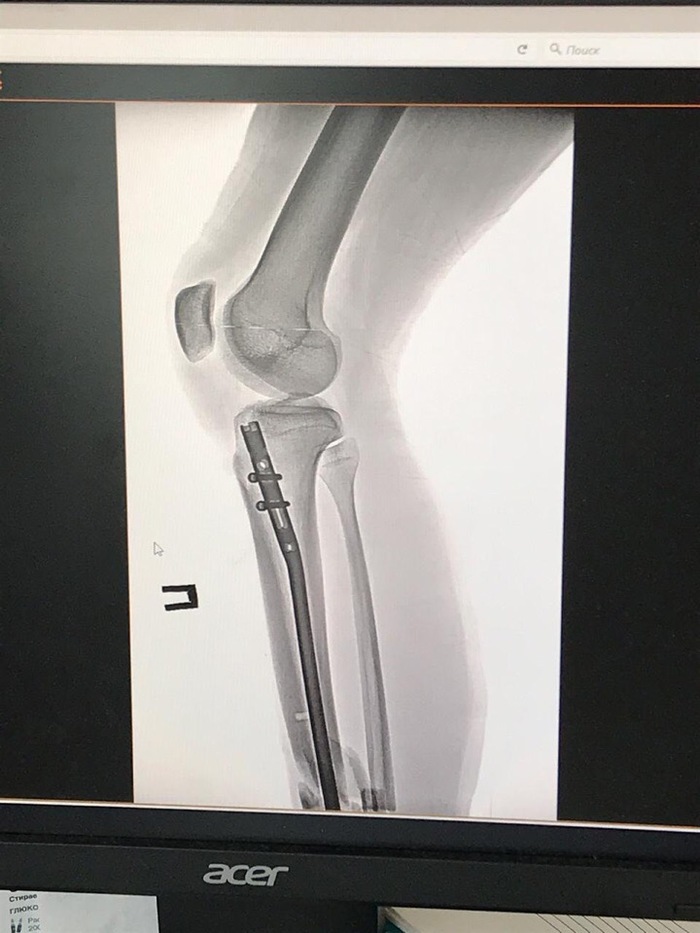

Почти два месяца сотрудник оренбургского батутного клуба «Отрыв» восстанавливается после тяжелой травмы. 22-летний Олег Щарихин во время демонстрационных прыжков на батуте получил открытый перелом голени. Спортсмен рухнул на сетку прямо на глазах у посетителей клуба. Ему оказали первую медицинскую помощь и доставали в больницу на машине скорой помощи. Все это время молодой спортсмен добивается от клуба компенсации или выплаты больничного, но руководство «Отрыва» отказывается признать травму производственной.

Далее два месяца и две сложных операции в ГКБ №4 Оренбурга, но до полного восстановления Олегу еще далеко.

По прогнозам медиков, на реабилитацию спортсмена может уйти около года. Его ногу буквально «собрали» из осколков при переломе голени. Дальнейшая карьера Олега Щарихина под большим вопросом. Он сегодня без работы, в сложном финансовом положении и пока все силы и средства тратит на то, чтобы реабилитироваться после тяжелейшей травмы.